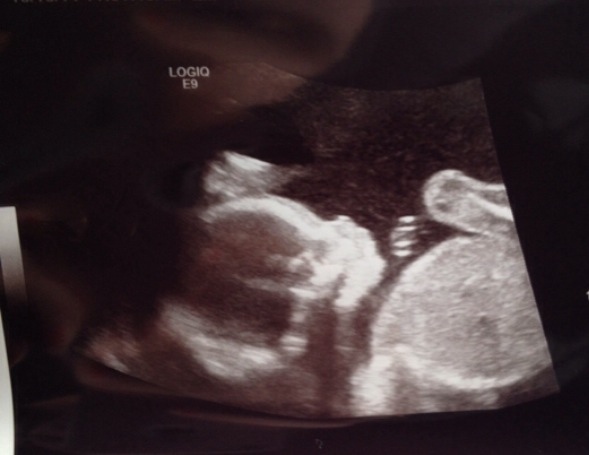

Any guesses based on skull theory? My 20 week scan! Thanks!!